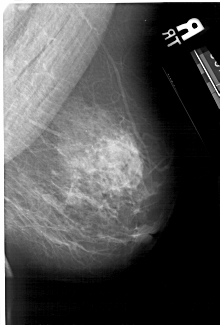

A_1631_1.LEFT_MLO

LEFT_MLO LINES 5491 PIXELS_PER_LINE 3331 BITS_PER_PIXEL 12 RESOLUTION 43.5 OVERLAY